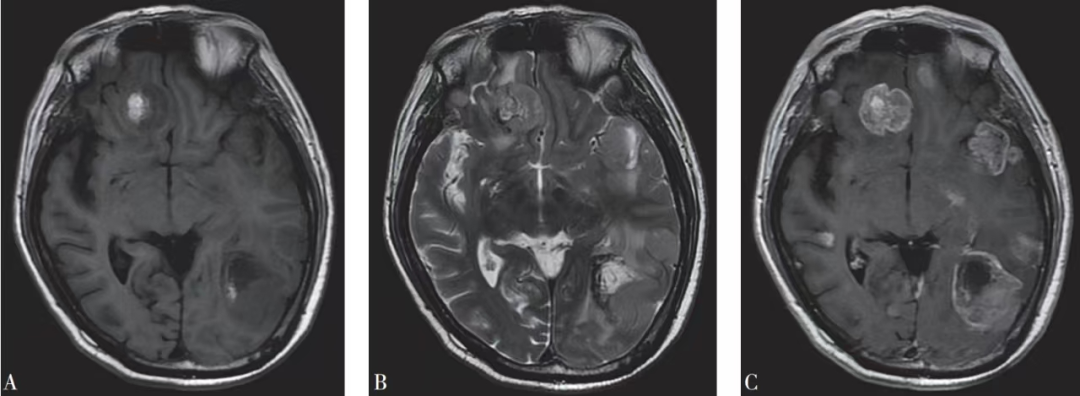

腦轉(zhuǎn)移瘤是常見的中樞神經(jīng)系統(tǒng)腫瘤,20%–40%的惡性腫瘤發(fā)展過程中會出現(xiàn)腦轉(zhuǎn)移,隨著影像技術(shù)的不斷進(jìn)步及惡性腫瘤患者生存期延長,腦轉(zhuǎn)移瘤發(fā)生率不斷上升。腦轉(zhuǎn)移瘤的患者一般預(yù)后較差,如果不接受有效的治療,多數(shù)會在數(shù)月乃至數(shù)周內(nèi)死亡。手術(shù)是腦轉(zhuǎn)移瘤治療方法之一,但腦轉(zhuǎn)移瘤質(zhì)地與腦組織不同,瘤周常有明顯腦組織水腫帶,水腫范圍比腫瘤本身大幾倍,甚至幾十倍。再加上腦轉(zhuǎn)移瘤侵襲性的生長方式行為,在進(jìn)行手術(shù)治療時(shí)很難確定腫瘤的邊界。

腦轉(zhuǎn)移瘤瘤周水腫帶示例